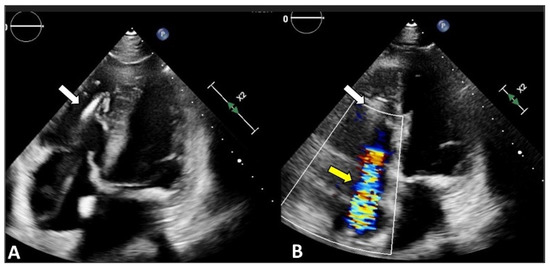

2.1. Two-Dimensional and Three-Dimensional Transthoracic and Transesophageal Echocardiography

4.1. Two-Dimensional and Three-Dimensional Transthoracic and Transesophageal Echocardiography